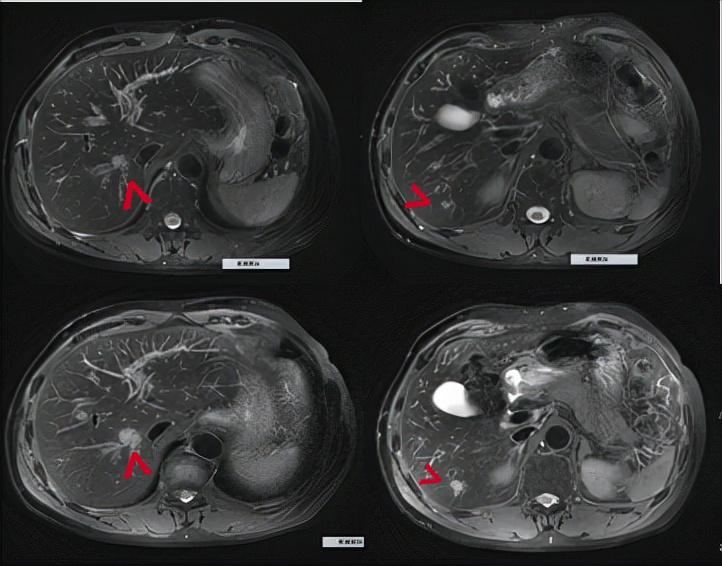

2020年11月复查上腹部MRI示:肝内多发转移灶较前增大,考虑治疗进展。

临床判断:鼻咽癌肝内多发转移免疫治疗后寡进展。

MRI示:肝内病灶较前增大,显示为寡进展。上图:耐药前;下图:耐药后

2020年11月:局部影像引导容积调强放疗,50Gy/20F/4w,替吉奥同步化疗2周期。

2020年12月至今:替吉奥维持治疗。

疗效评价:大PR。

MRI示:肝内病灶放疗后明显缩小。上图:放疗前;下图:放疗后